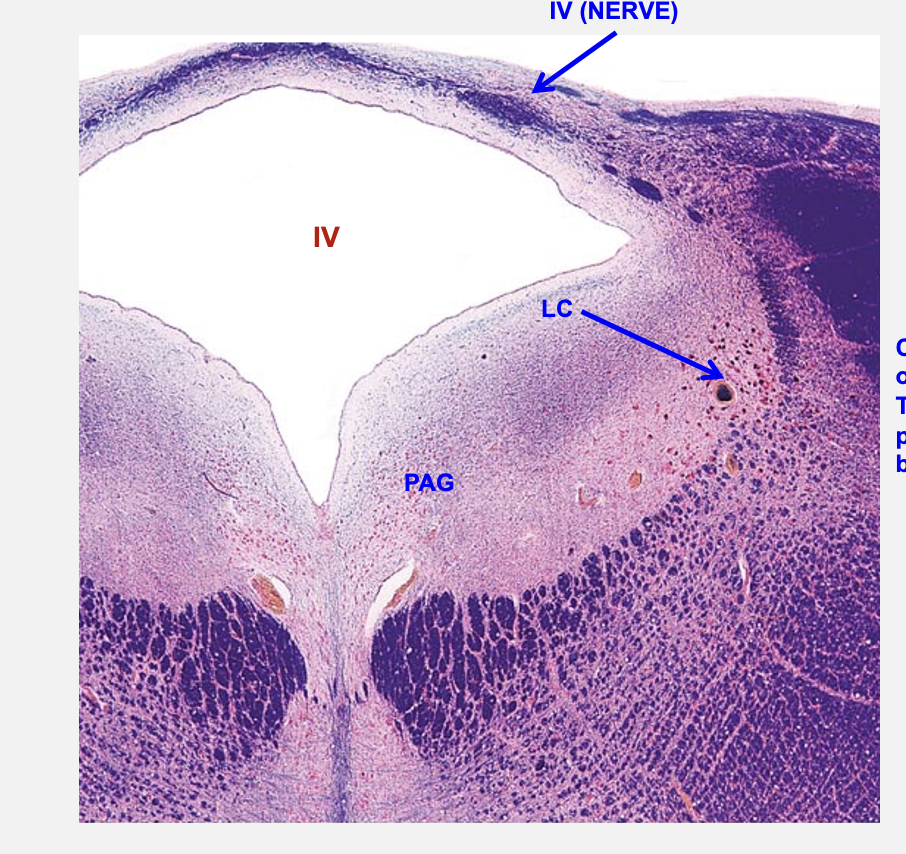

cerebral aquduct

periaqueductal gray

troclear nucleus

located in caudal midbrain; troclear nerve is the only cranial nerve that exits from dorsal aspect of brain; also only cranial nerve that crosses to innervate contralateral muscle

locus ceruleus

primary source of norepinephrine to the brain; important for alerting responses